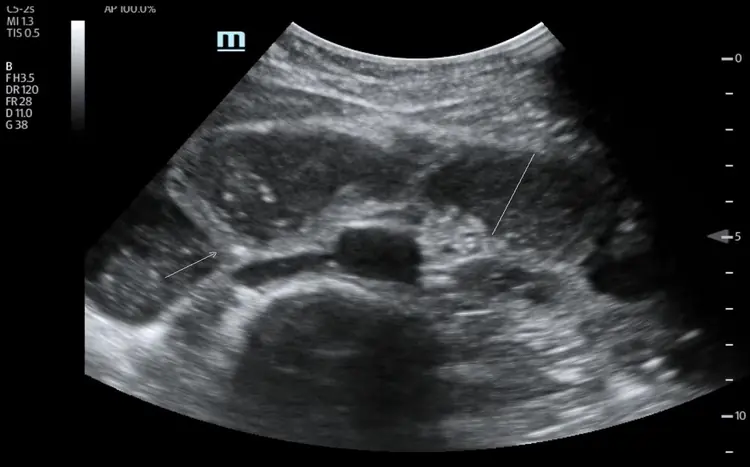

Occlusion : identifier le blocage en urgence.